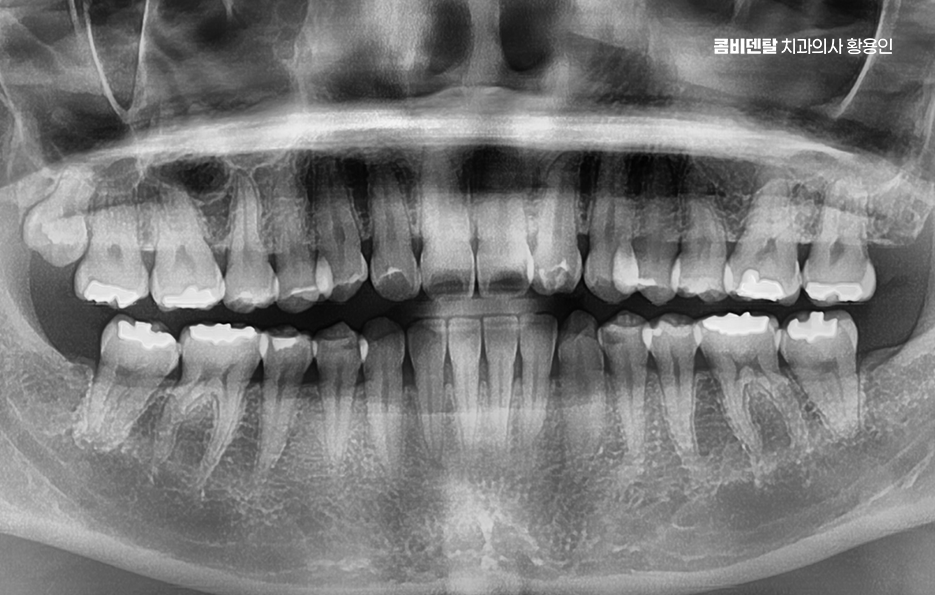

출처 아카이브 열기처음 인레이 치료를 받았을 때만 해도, 마음이 꽤나 편안했어요. 치료 전까지 며칠 동안 어금니 안쪽이 묘하게 시큰거리면서 음식을 씹을 때마다 찌릿한 통증이 있었어요 그래서 나도 모르게 반대편으로만 씹는 버릇이 생길 정도였는데, 결국 치과에 가서 충치 진단을 받고 난 후 인레이 보철 치료를 할 때만 해도 이제 괜찮아지겠구나 하는 안도감이 먼저 들었어요.

그런데 그 안정감이 오래가지 않았어요. 치료 후 몇 달 정도는 아무렇지 않게 지냈어요. 어느 쪽으로 씹든 상관없었고 인레이가 내 치아 안에 있다는 사실조차 잊고 지낼 만큼 자연스럽게 잘 적응하고 있다고 느꼈어요. 하지만 어느 날부터인지 그 부위 주변에서 묘한 이물감이 느껴지기 시작했어요.

이처럼 치과 치료는 한 번 받고나면 별다른 통증이 없다면 치료도 잘되었고 이제 원래대로 살면 되겠구나 하면서 보철물에 대해 잊고 지내는 경우가 많이 있는데요. 하지만 보철물에도 수명이 있고 환자의 생활습관 및 관리에 따라서 보철물 수명은 더 짧아지는 경우도 있어요

특히 인레이 치료를 받은 지 오래됐는데 어느 날 갑자기 그 부위에서 인레이 치료 후 통증이 느껴진다면, 단순한 불편감을 넘어서서 그 안에 숨어 있는 문제를 다시 살펴봐야 하는 신호일 수 있는 거예요. 인레이라는 건 충치가 진행됐던 치아의 손상 부위를 제거하고 그 빈 공간에 금이나 세라믹 재질로 만든 인레이를 정밀하게 맞춰서 채워 넣는 치료 방식이라 할 수 있는데요

충치가 깊고 넓은 손상이 있을 때는 크라운을 씌우는 게 맞지만, 상대적으로 보존할 수 있는 자연치아가 많고, 신경치료를 동반하지 않아도 되는 상황에서 많이 선택되는 치료가 인레이이며 이렇게 치료 받은 인레이가 치료 직후가 아니라 수년이 지난 후에 인레이 치료 후 통증이 생기는 경우라면, 그 원인은 다양하지만 대체적으로는 보철물 아래쪽에서 발생하는 2차 충치나 인레이와 치아 사이의 미세한 틈, 또는 신경 손상, 잇몸질환으로 인한 문제일 가능성이 높다고 할 수 있어요